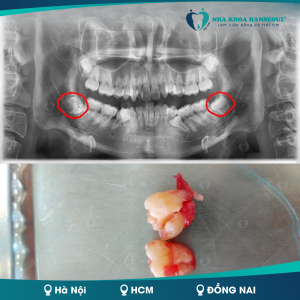

Bị sâu răng hàm trên và hàm dưới gây ra áp xe răng

Sâu răng hàm trên và hàm dưới được xem là tình trạng nặng nhất của sâu răng, lúc này vị trí sâu đã lan rộng đến tất cả răng hàm và hình thành những búi mủ ở vị trí của chân răng, còn được gọi là áp xe răng. Điều này gây ra cảm giác đau đớn nghiêm trọng và dễ dẫn đến các biến chứng nhiễm trùng khá nguy hiểm.